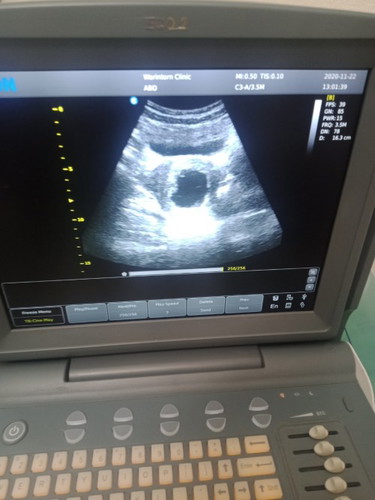

ท้องลมหรือเปล่าคะท้อง2เดือนหมอบอกไม่พบตัวเด็กเลย😥😥😥 กังวลมากค่ะท้องเล็กด้วย อัลตร้าซาวด์ครั้งแรก

เคยเป็นค่ะตอนซาวด์หน้าท้องหมอไม่เจอตัวเด็ด พอซาวด์ช่องคลอดถึงเจอตัวน้องค่ะ